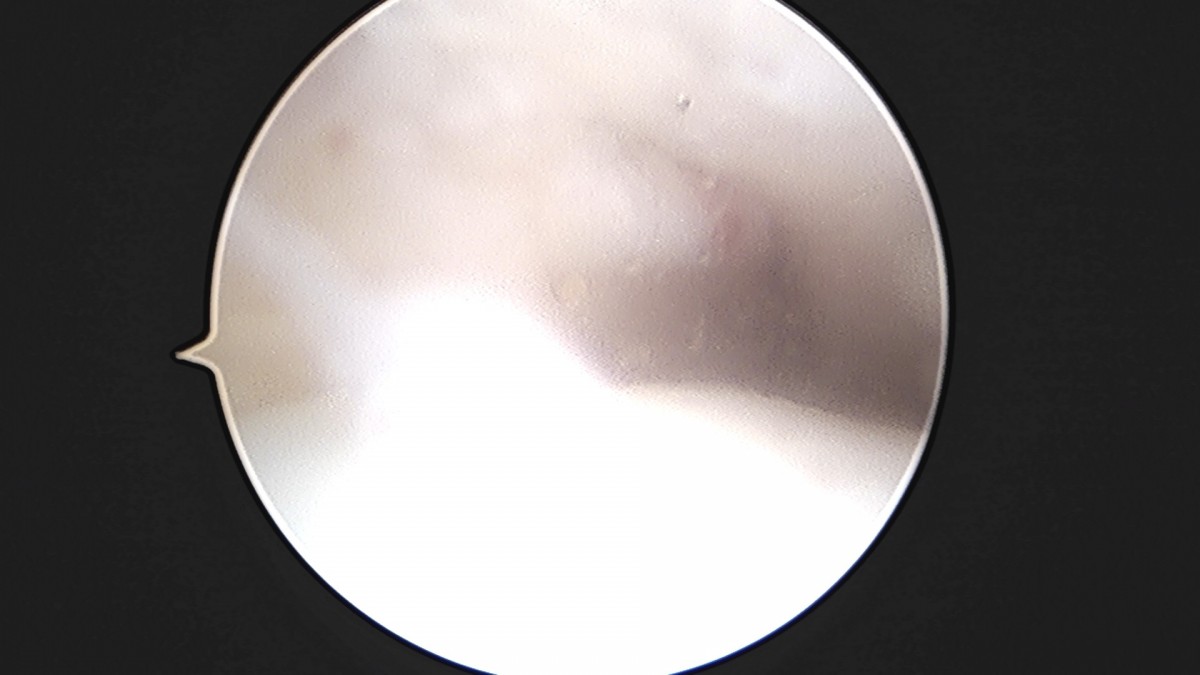

이재상원장님 발목 인대 봉합술 이지O 환자

작성자 최고관리자 댓글 0건 조회 681회 작성일 25-09-16 16:26